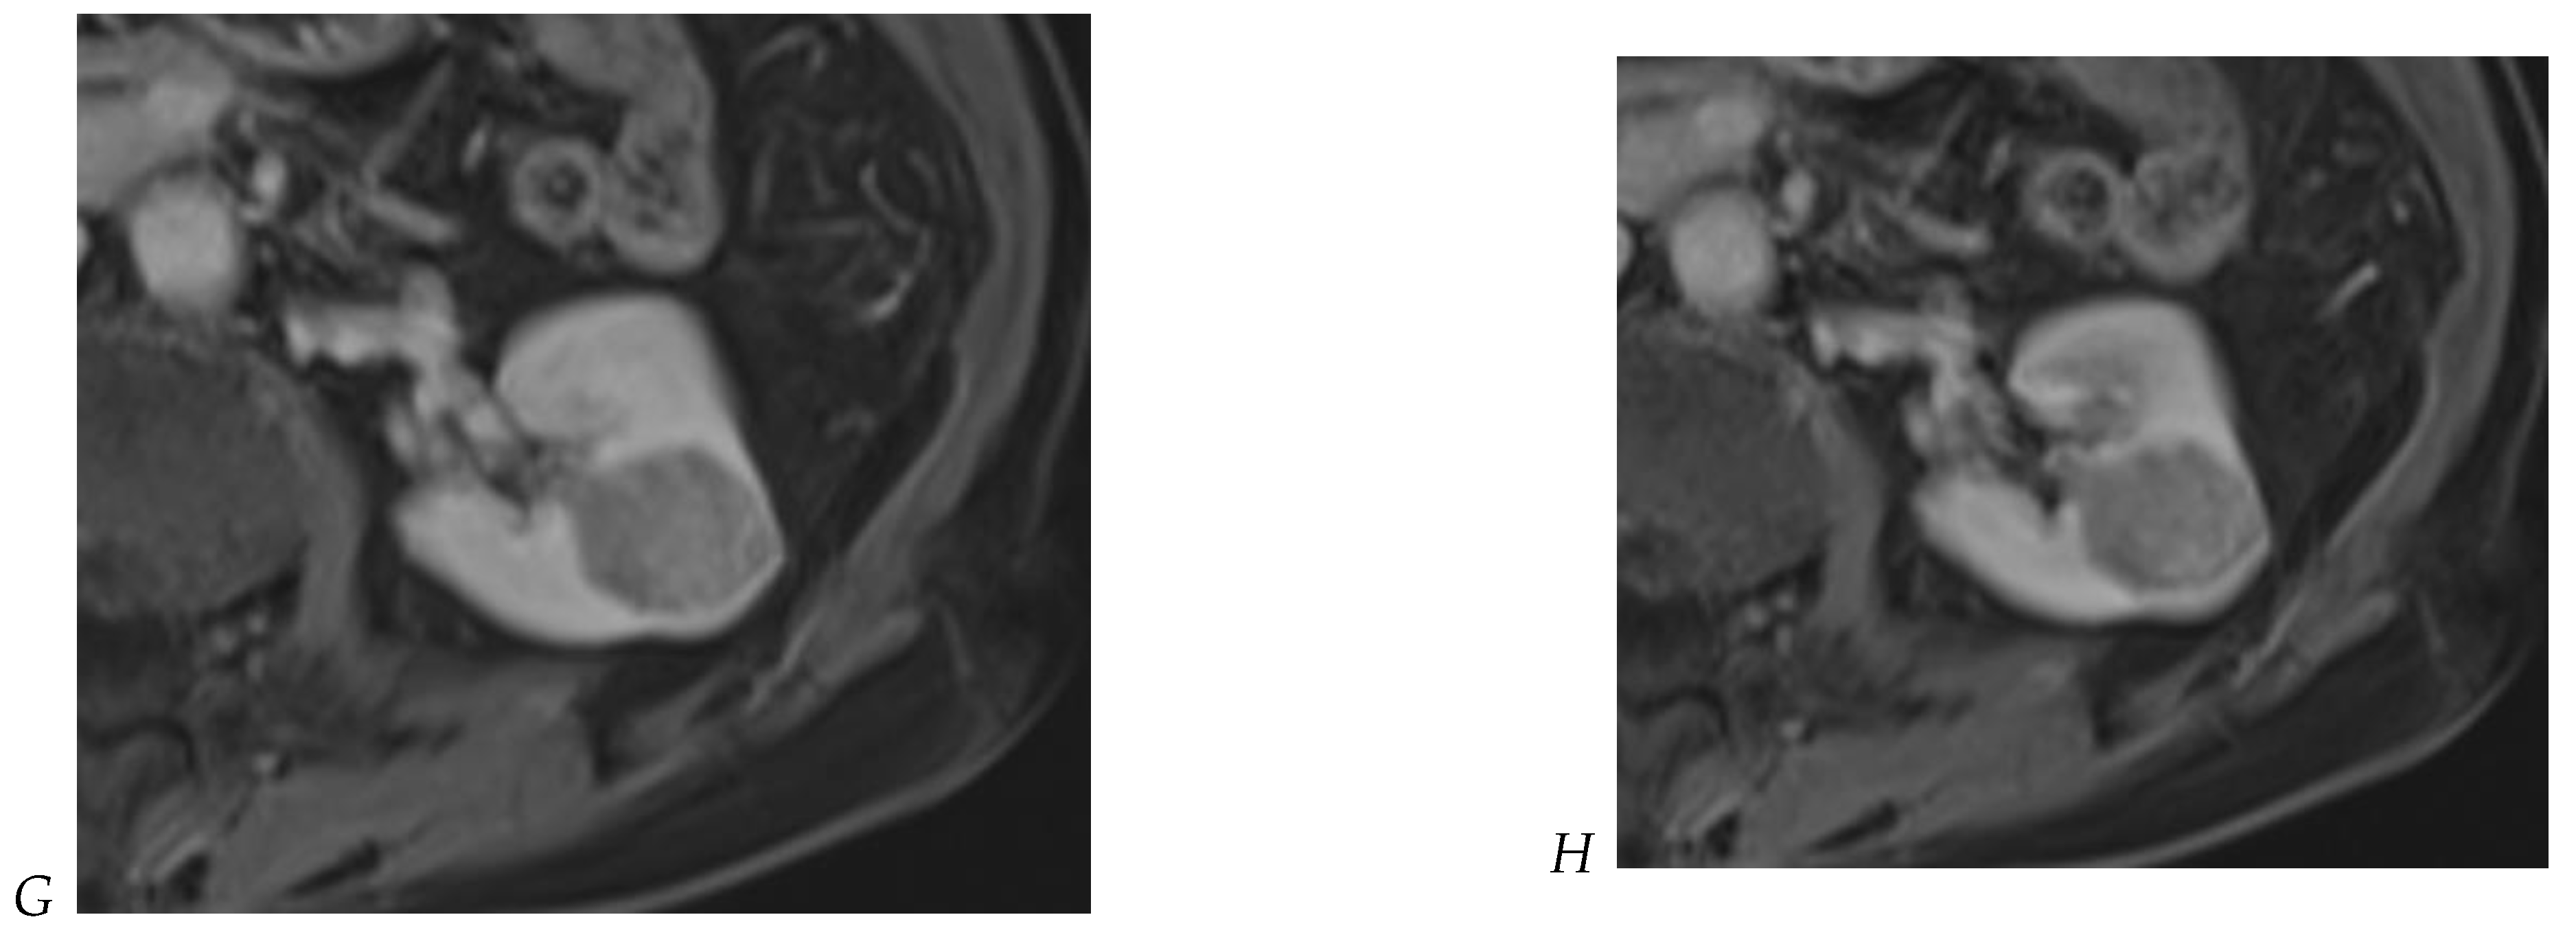

Figure 6.

Fat-poor angiomyolipoma in the right kidney of a 46-year-old-man. (A) Coronal T2-weighted fast SE image shows the low signal intensity of the lesion compared with the renal parenchyma. Transverse in-phase (B,C) opposed-phase MR images show a significant loss of signal intensity on the opposed-phase image. (D) The ADC map shows marked restriction of tumor diffusion into the renal mass. Transverse gadolinium-enhanced T1-weighted gradient-echo spoiled MR images in (E) corticomedullary, (F) nephrographic, (G) and delayed phase images show early enhancement and rapid washout.

Figure 7.

Papillary renal cell carcinoma in the right kidney of a 75-year-old-woman. (A) Axial T2-weighted fast SE image shows a homogeneous 1.8 cm mass in the posterolateral region of the right kidney, with a lower SI compared to renal parenchyma. Transverse in-phase (B,C) opposed-phase MR images do not show a significant signal loss on the opposed-phase image. (D) The ADC map shows restriction of tumor diffusion into the renal mass. Transverse nonenhanced (E) and gadolinium-enhanced T1-weighted gradient-echo spoiled MR images in (F) corticomedullary, (G) nephrographic, (H) and delayed phase images show progressive enhancement without washout; the mass is hypovascular compared to the renal cortex.